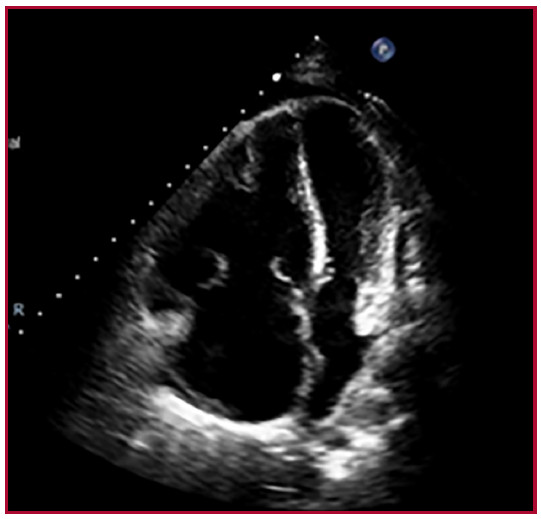

Se describe el caso de una paciente de sexo femenino de 20 años con diagnóstico previo de enfermedad mixta del tejido conectivo en 2018, sin seguimiento en los últimos 18 meses, tiroiditis de Hashimoto y bronquiectasias. Acudió a Guardia Externa por dolor abdominal, náuseas y diarrea. A su ingreso se constataron signos de insuficiencia cardíaca derecha (edemas en miembros inferiores, ingurgitación yugular sin colapso inspiratorio, reflujo hepatoyugular positivo y hepatomegalia), aumento de la intensidad del segundo ruido cardíaco a expensas del componente pulmonar, y soplo sistólico en foco tricuspídeo. El estudio diagnóstico inicial incluyó un electrocardiograma con signos de sobrecarga de cavidades derechas y bloqueo completo de rama derecha, y radiografía de tórax con aumento del segundo arco pulmonar derecho e índice cardiotorácico conservado. En el ecocardiograma Doppler se observó dilatación de cavidades derechas, disfunción grave del ventrículo derecho, insuficiencia tricuspídea grave con velocidad de regurgitación pico mayor que 4,5 metros por segundo (m/s), presión sistólica de la arteria pulmonar (PSAP) de 105 mm Hg, presión media de la arteria pulmonar (PAPm) de 55 mm Hg y derrame pericárdico leve. (Figura 1). Consecutivamente se realizó cateterismo cardíaco derecho que confirmó el diagnóstico de hipertensión arterial pulmonar (HAP) grave con presión media de aurícula derecha de 11 mm Hg, PAPm de 63 mm Hg, presión de enclavamiento pulmonar de 10 mm Hg, resistencia vascular pulmonar de 21 unidades Woods (UW), gradientes transpulmonar y diastólico de 53 mm Hg y 43 mm Hg respectivamente, gasto cardiaco (GC) de 3,20 L/min , índice cardíaco (IC) de 2,6 L/min/m2, índice de volumen sistólico (IVS) 23 ml/lat/m2, saturación venosa mixta de 65% y saturación arterial de 97%. Por falla ventricular derecha marcada, inició infusión endovenosa continua de furosemida sin respuesta favorable, soporte inotrópico con milrinona a dosis máxima que posteriormente se rotó a levosimendán 0.1 ug/kg/ min y soporte vasopresor con noradrenalina a dosis intermedias. La paciente evolucionó de forma desfavorable con signos de bajo gasto cardíaco y falla grave del ventrículo derecho. Debido a la falta de acceso inmediato a prostanoides parenterales, se realizó septostomía transeptal con balón de forma exitosa (fenestración de 5 mm) (Figura 2). La paciente presentó mejoría del estado clínico, con derivación precoz a un centro de mayor complejidad para valoración pretrasplante e inicio de infusión continua de epoprostenol endovenoso, con dosis en ascenso hasta 12 ng/kg/min, previo destete y suspensión de inotrópicos, e inicio de ambrisentán 10 mg y tadalafilo 10 mg con buena tolerancia. En el ecocardiograma Doppler control presentó dilatación moderada de cavidades derechas, PSAP de 70 mm Hg y solución de continuidad interauricular de 0,9 mm. (Figura 3) El cateterismo cardiaco evolutivo demostró descenso de la PAPm, RVP y mejoría del GC e IC (43 mm Hg, 7,3 UW, 4,8 l/min y 3,6 l/min/m2, respectivamente). Fue valorada por el servicio de Reumatología que confirmó el diagnóstico de lupus eritematoso sistémico por criterios clínicos e inmunológicos y nefritis lúpica grado II por biopsia renal.